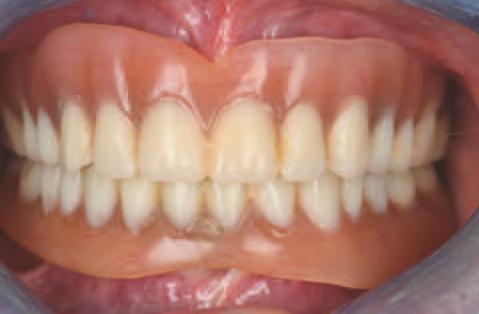

15. Vedere extraorală a restaurărilor finale livrate.

16. Vedere intraorală a restaurărilor finale mandibulare livrate.

În cab net, restaurăr le prov zor au fost deșurubate ș îndepărtate d n cav tatea orală pentru ca restaurăr le f nale să poată f l vrate ș strânse cu un cuplu de 15 Ncm, conform recomandăr producătorulu (f g. 15,16). Ajustăr le ocluzale f nale au fost m n me ș efectuate ntraoral pr ntr-o ultmă lustru re a zonelor ajustate.